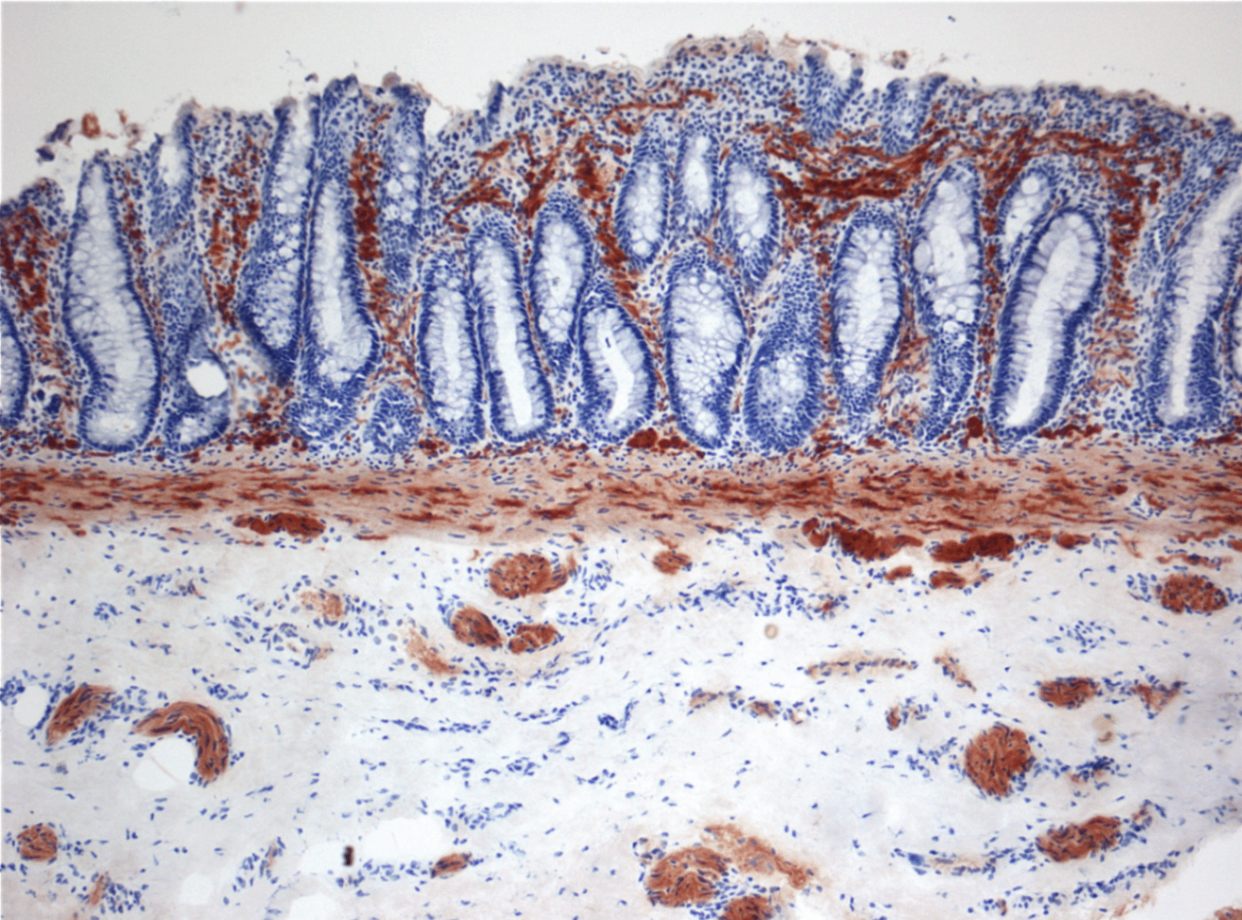

3) 조직학적 특징

신경절세포 부재

AchE 염색 시 신경섬유 과다 증가

• 항문 생검으로 진단

Hirschsprung acetylcholine, Wikimedia Commons